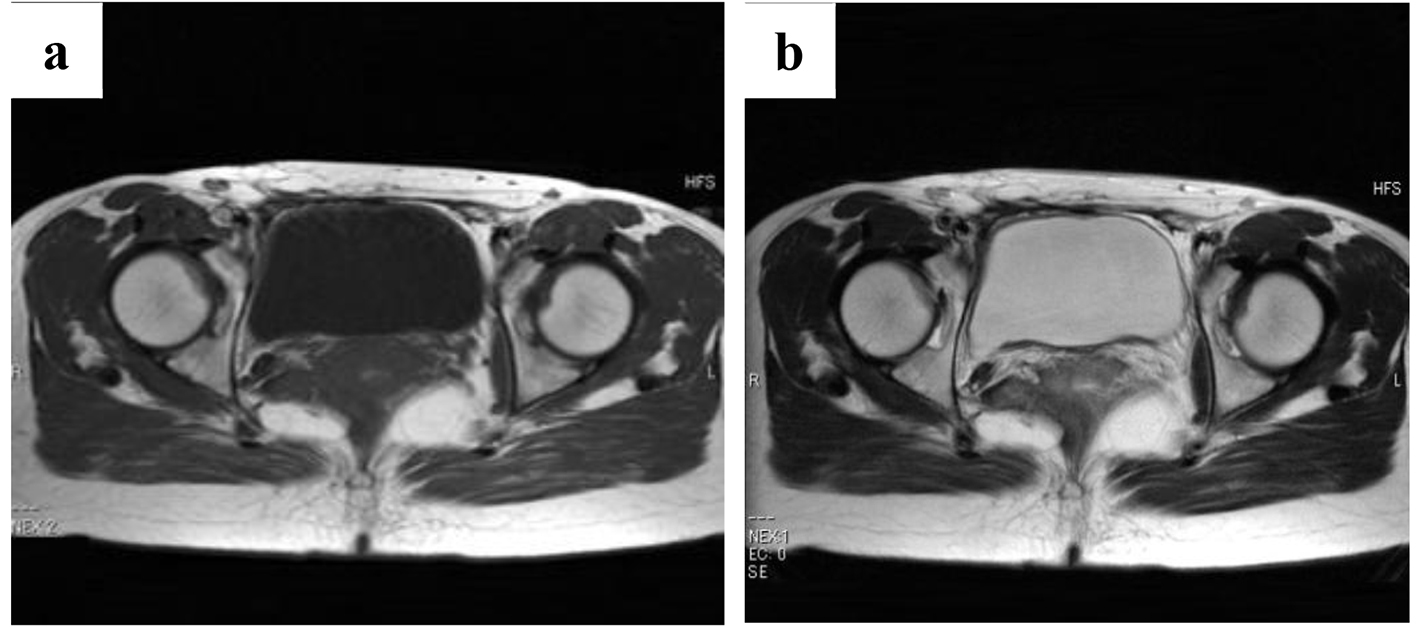

Figure 5. Magnetic resonance images of the two masses obtained at 5 years and 4 months after surgery (a: T1-weighted images; b: T2-weighted images). The masses have not increased in size.

Figure 6. Magnetic resonance images obtained at 8 years and 4 months after surgery (a: T1-weighted images; b: T2-weighted images; c: gadolinium contrast). The enhanced masses have disappeared.